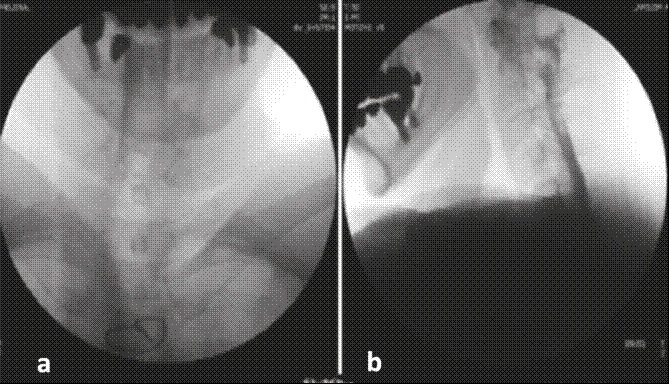

Mujer de 62 años con cuadro de cuatro meses de evolución consistente en cefalea holocraneana constante de predominio occipital que se exacerbaba con la sedestación y la bipedestación, con intensidad máxima referida como 9/10 en la escala verbal análoga (EVA) y que disminuía a 0/10 con la posición supina. Se asociaba a náuseas y vómitos. Se hizo RM cerebral con hallazgos compatibles con hipotensión endocraneana. Como antecedente informó enfermedad coronaria que requirió revascularización miocárdica 12 años antes; en la actualidad no recibe tratamiento farmacológico. El examen físico y el neurológico fueron normales sin signos meníngeos ni de focalización. Se planteó el diagnóstico de síndrome de hipotensión endocraneana probablemente secundario a una fístula espontánea de líquido cefalorraquídeo. Se hizo cisternografía que evidenció extravasación de medio de contraste principalmente a nivel de C7 izquierdo. Con tal diagnóstico se optó, en una junta médica multidisciplinaria, por un abordaje dorsal para aplicar un parche hemático bajo visión directa con fluoroscopia. En el quirófano se hizo un abordaje interlaminar a nivel de T2 mediante la técnica de pérdida de la resistencia con aire y aguja Tuohy n.º 17; sin embargo, en el momento de efectuar el epidurograma se observó migración del medio de contraste al espacio subdural por lo que se suspendió el procedimiento (Figuras 3a y 3b).

El medio de contraste en un epidurograma normal da un patrón que se asemeja a un árbol de Navidad; su distribución puede ser asimétrica y se observan burbujas dentro de la mancha de medio de contraste, a diferencia del patrón homogéneo del contraste observado cuando la inyección es subdural, donde se distribuye ampliamente a muchos segmentos de la columna vertebral hacia arriba y hacia abajo en una columna estrecha, por lo que la imagen característica se ha denominado ''rieles de ferrocarril'' patrón visto en la proyección anteroposterior, en la que se observan dos finas columnas laterales, resultado de que el espacio subdural es más ancho lateralmente, lo que permite la acumulación allí del contraste, mientras que en la imagen lateral las columnas de contraste se localizan dorsal y ventralmente. Una opacidad mal definida entre las columnas representa un pequeño volumen de contraste subdural 21, como se pudo detectar a tiempo en el segundo caso (Figura 3a), y, de esta forma, evitar las complicaciones de una inyección en el espacio equivocado.